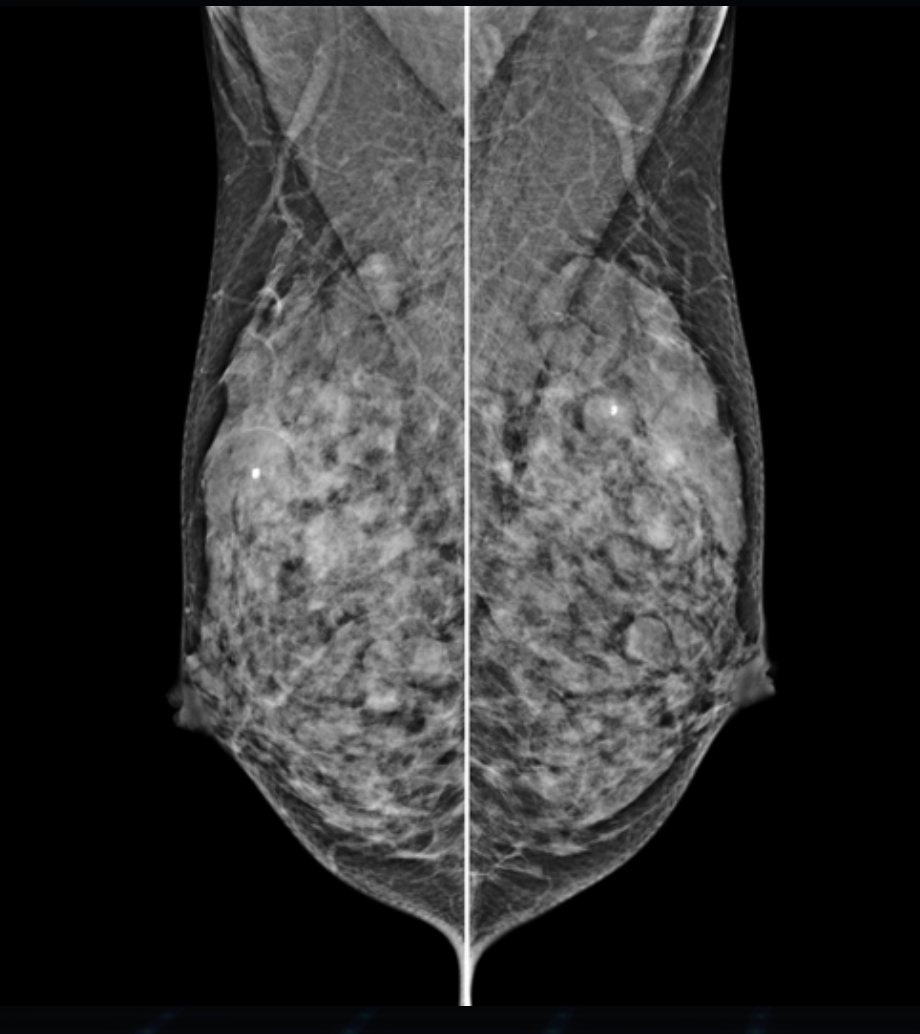

Detektor cyfrowy FFDM

Nowoczesny detektor cyfrowy o wysokiej czułości i rozdzielczości, zapewnia precyzyjne odwzorowanie detali anatomicznych, w tym mikrozwapnień i zmian strukturalnych miąższu.